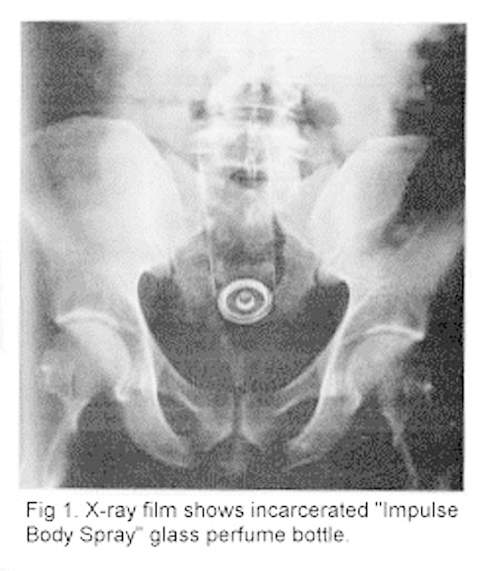

這個長條形的物體不是電動蘇格蘭,而是一罐噴霧式的香水~